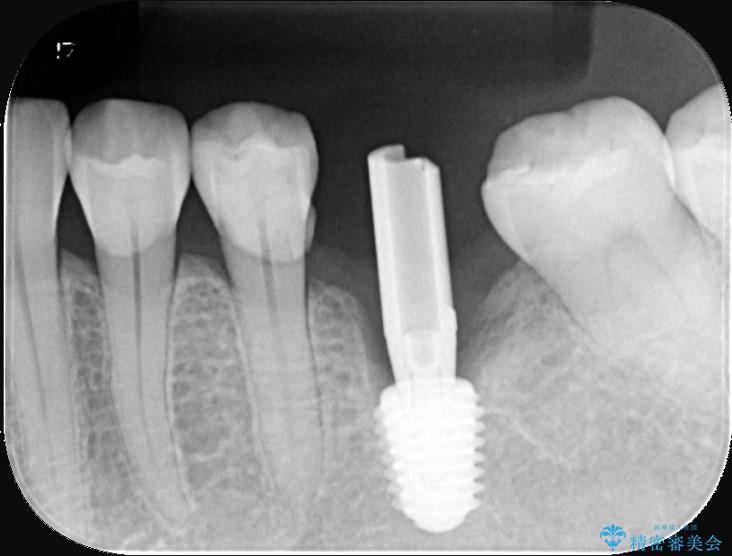

精密検査の結果、高さに制限はあるが厚みは十分に確保されていることが確認されました。

骨を増やす治療は行わず、残っている骨を最大限に活用し治療を行うこととしました。

一般的に、骨が少ない場所への埋入は高度な技術を要しますが、今回は適切なサイズ(8.5mm)を選択し、埋入する深さを緻密にコントロールすることで、周囲の神経や重要な組織を傷つけることなく安全に処置を完了しました。